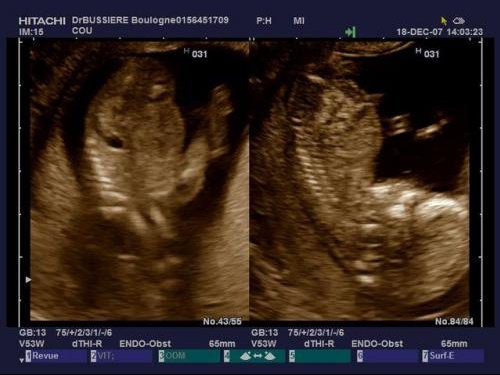

Battement coeur bebe fille garcon. Fille ou garçon. Mais je me surprends à chercher des indices là où il n y en a. Coucou j ai un petite question j ai entendu parler qu on pouvait savoir le sexe de bebe par rapport au battement de cœur par minute et qu ils faisaient comme ça dans le temps. Dans les temps anciens cette hypothèse avait une certaine part de probabilité car les gens remarquaient que dans le ventre de la mère le cœur des filles battait différemment du cœur des garçons.

Battements du coeur. Selon vous filles ou garcon. Alors moi a 6 sa 3 son cœur battait a 127 bpm et a 8 sa 3 entre 160 et 180 bpm. Battement du cœur fille ou garcon.

Battement coeur foetus fille ou garcon. Deviner le sexe grâce au battement de cœur de bebe.